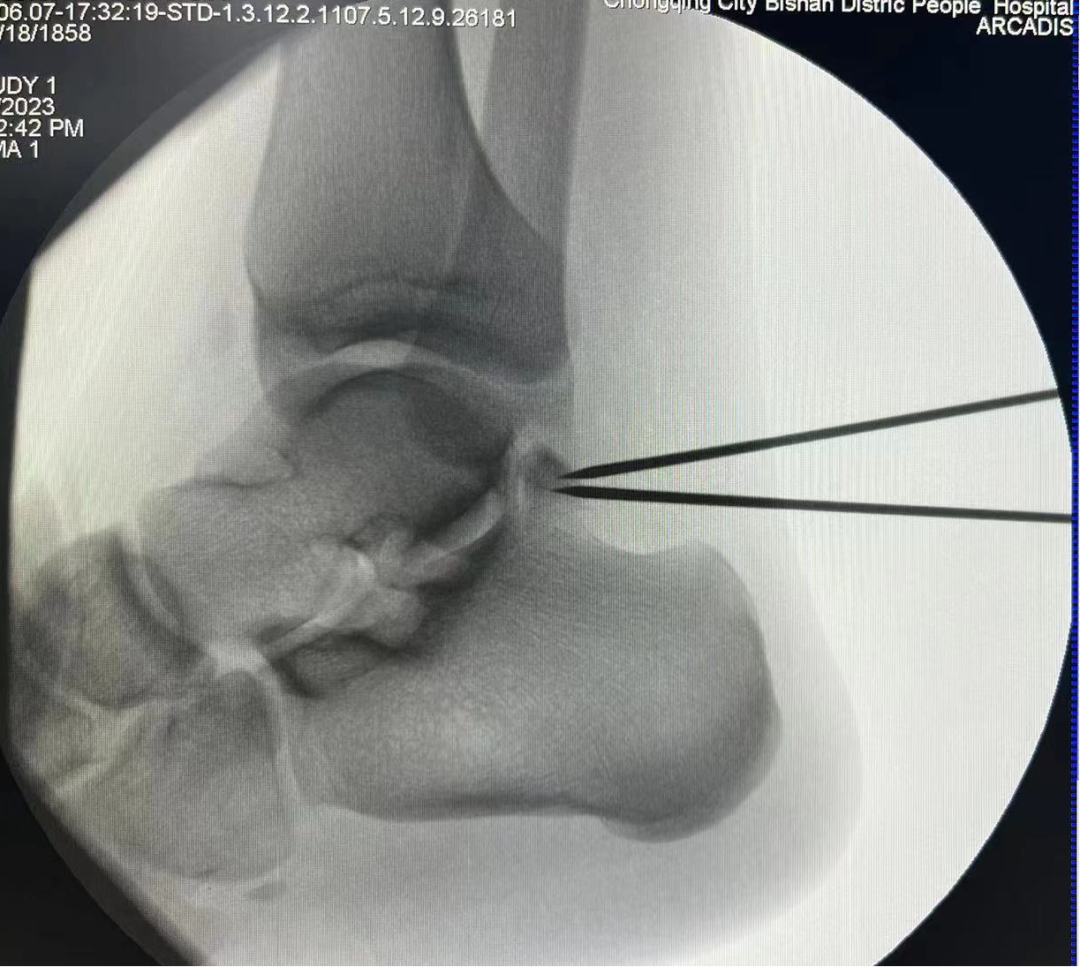

術中C臂定位病灶位置